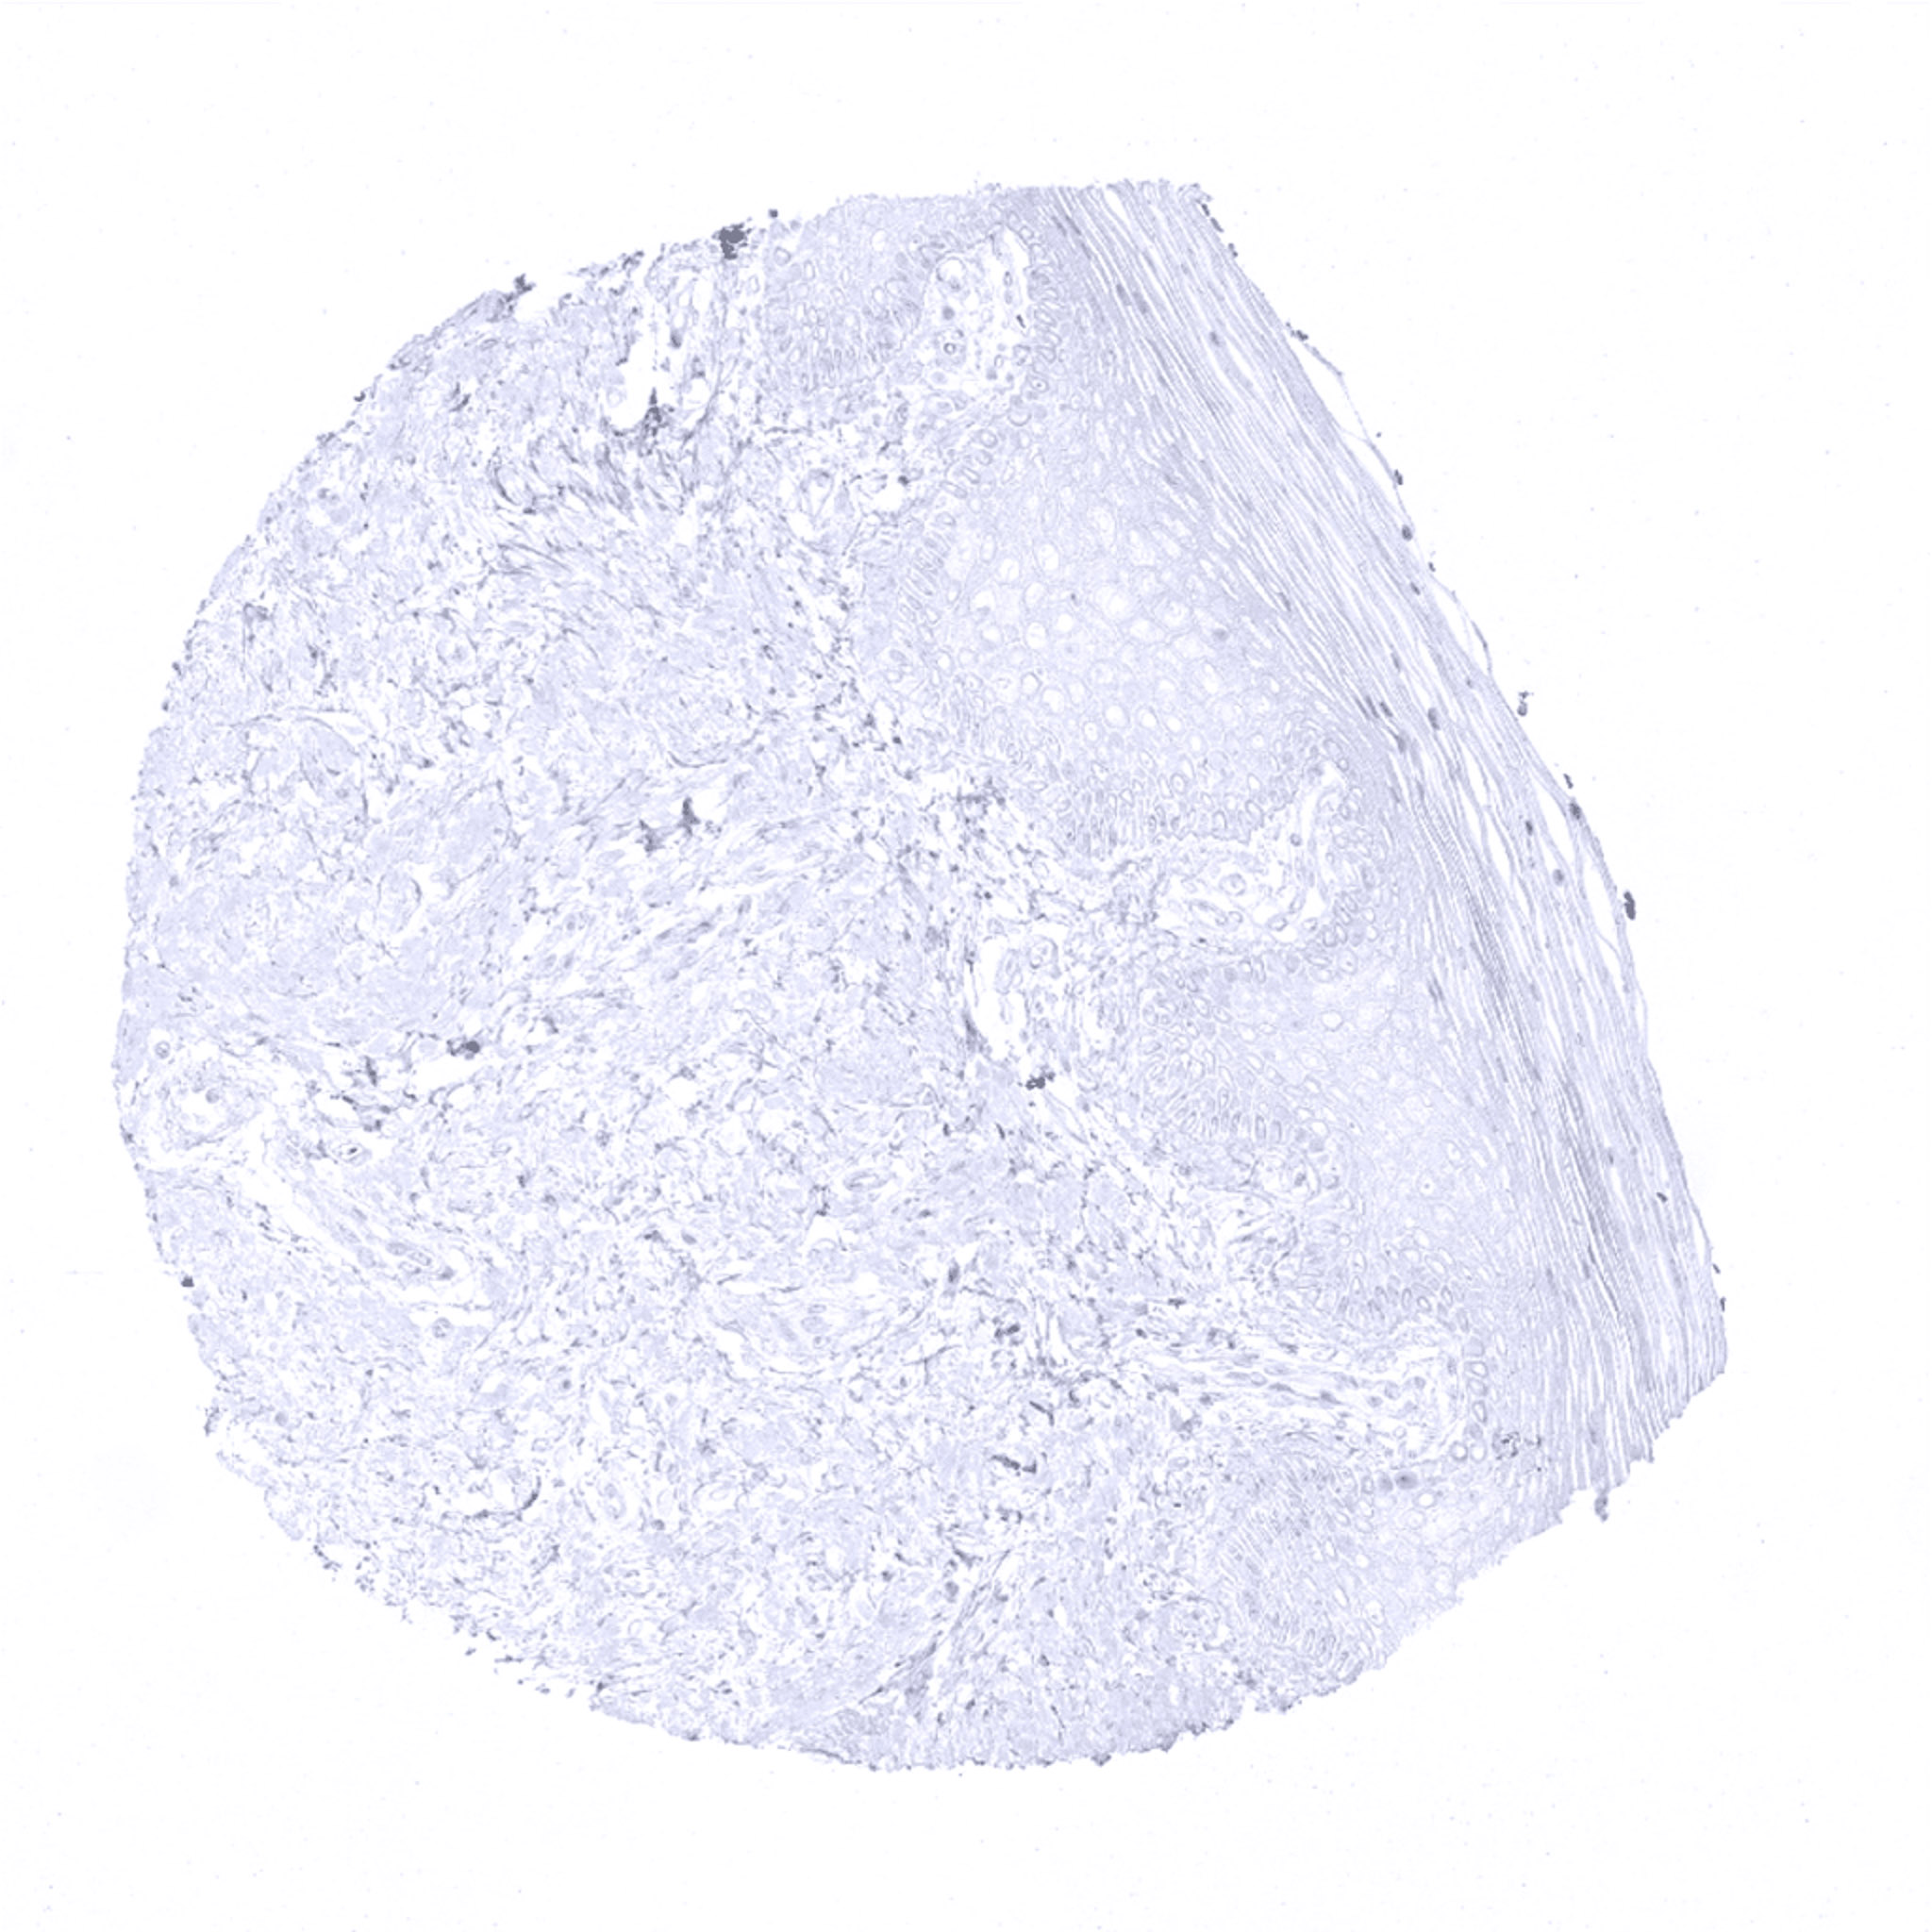

Lymph node